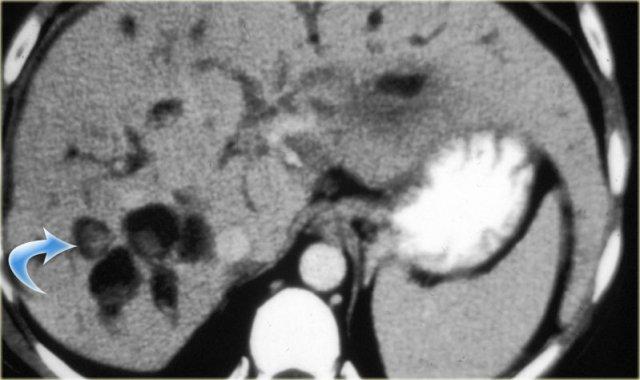

Bên trái là hình ảnh CT của cùng bệnh nhân.

Lưu ý dấu hiệu chấm trung tâm và tổn thương theo phân thùy.

Bệnh nhân này có xơ gan kèm lách to do tăng áp lực tĩnh mạch cửa.

Giãn ống mật ngoài gan hiện diện trong 53% các trường hợp, thứ phát do viêm đường mật và sự di chuyển của sỏi hoặc bùn mật.

Đây là các dấu hiệu thứ phát, không phải là một phần của bệnh nguyên phát.